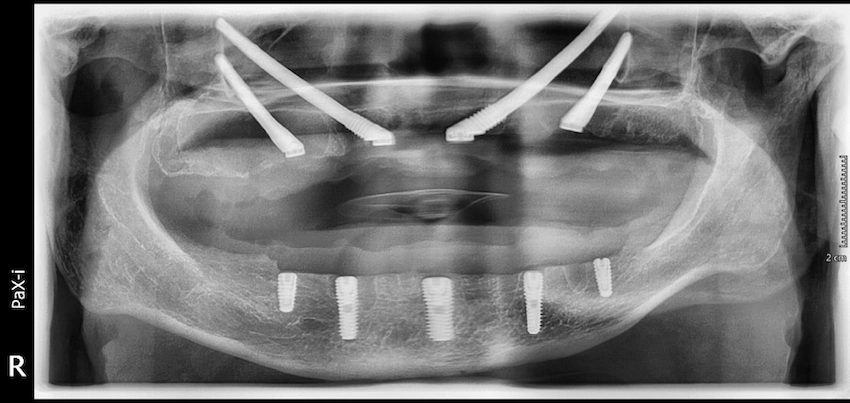

Subperiostal implantlar ve zigomatik implantlar karşılaştırması

Zigomatik implantlar, subperiostal implantların alt sınıfını oluşturan ve ciddi kemik kaybı yaşayan hastalarda uygulanan bir yöntemdir. Subperiostal implantlar kemiğin üzerinde yer alırken, zigomatik implantlar elmacık kemiklerine sabitlenir. Her iki tür de, kemik hacmi yetersiz olan hastalara etkili tedavi imkanı sunar ve en iyi seçeneği belirlemek için kapsamlı tanı ve değerlendirme gerekir.